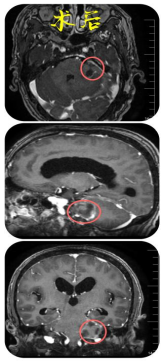

术后,显示左侧听神经鞘瘤已消失。

术后,患者身体恢复良好,无明显后遗症,康复出院。重新回归正常生活的李某为了表达内心的感激之情,委托家属特意定制了这面锦旗送到神经外科,患者家属感谢说:“是郴州市第四人民医院医护人员给了我们家人第二次生命,你们不仅医术精湛,对患者更是关怀备至,让我们在绝望的时候看到了希望。”